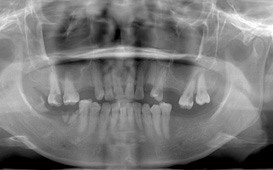

咬合崩塌 / 上牙下墜 / 下牙上長 / 前牙飆出 / 傾倒 / 蛀牙 / 牙周病缺牙未重建 - 臨床實例

上面的牙往下墜,下面的牙往上長,前面的牙往外飆 – 咬合崩塌牙周病,蛀牙;這些現象必然發生,時間越久,問題越大,而且除非藉由矯正及其他牙科治療,無法修正。

後續矯正以建立出已喪失的空間